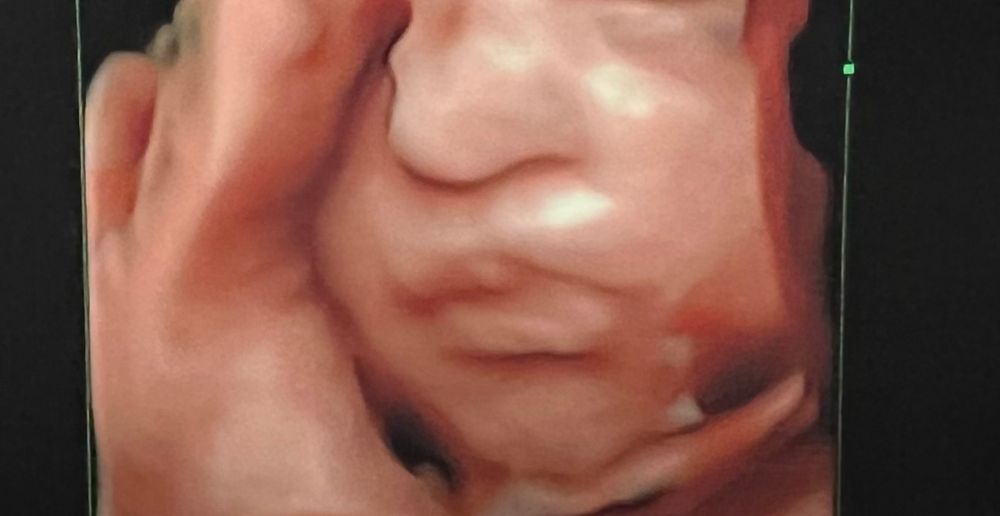

4D узи 3 скрининг

УЗИ, КТГ, доплерСегодня шла на 3 скрининг, все у нас хорошо🤗 Сыночек Опережает на неделю. Но вот только фотки немного озадачили.. он не похож на нас с мужем, нос огромный.. У кого было так же на узи, но носик вышел небольшим?😁